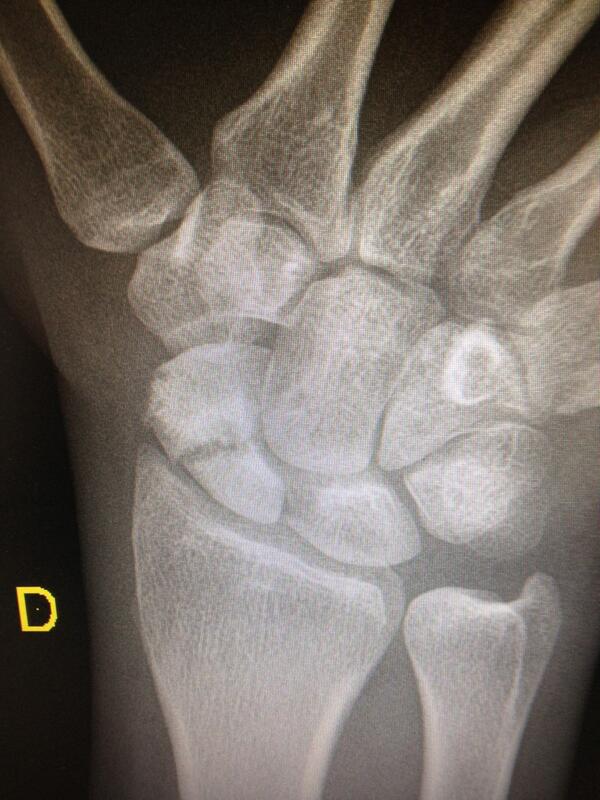

Cirugía de Mano y Traumatología: Pruebas Radiológicas para la fractura

Source: manoytrauma.blogspot.com